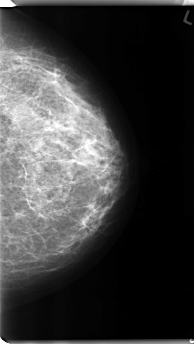

C_0136_1.LEFT_CC

LEFT_CC LINES 4816 PIXELS_PER_LINE 2712 BITS_PER_PIXEL 12 RESOLUTION 50 NON_OVERLAY